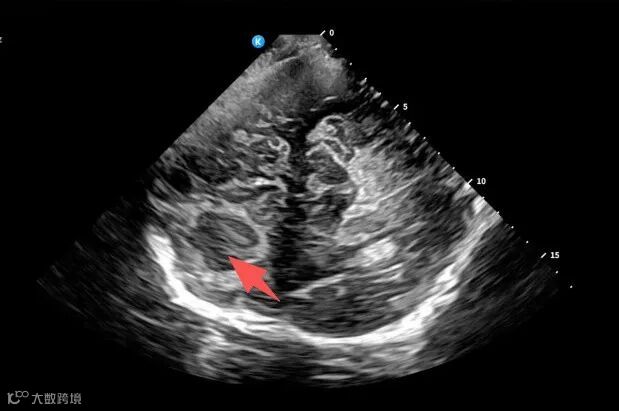

超声屏幕上的图像清晰展示了脓肿的位置、大小及其与周围血管的关系。

随着穿刺引流管在超声的实时引导下缓缓进入,术者可以清晰地观察到引流管的轨迹正精准地朝向脓肿目标。

在穿刺成功的瞬间,超声图像实时显示了脓肿被成功穿刺以及脓液被顺利抽吸和反复冲洗的过程。